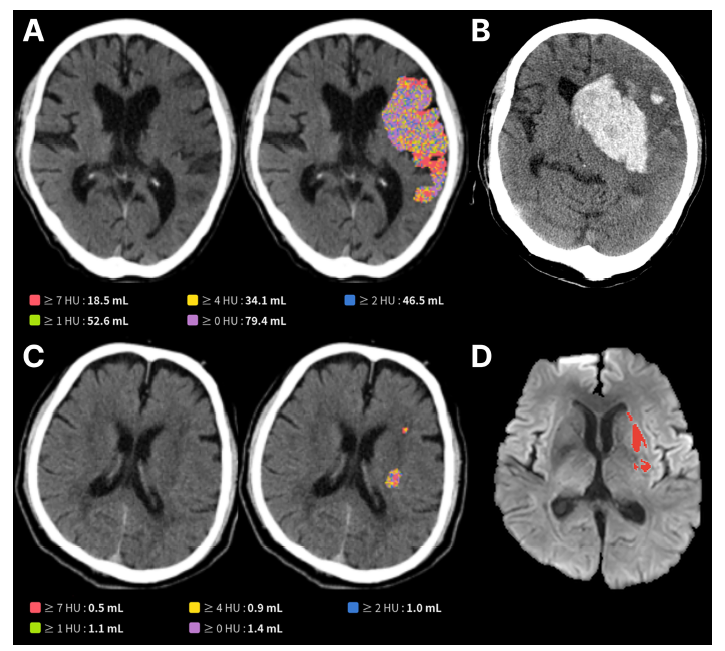

| AI 뇌경색 최신 연구 논문 'Frontiers in Neuroscience' 발표 자료. 제이엘케이 제공 |

제이엘케이는 자사의 뇌경색 병변 검출 AI 모델이 대규모 임상 검증을 통해 뇌 손상 범위를 정확히 정량화하고, 환자의 기능적 회복 수준과 합병증 위험까지 예측할 수 있음을 증명했다고 11일 밝혔다.

제이엘케이의 AI 모델은 이러한 문제를 해결하기 위해 개발됐다. 다수의 뇌경색 환자 NCCT와 확산강조영상(DWI) 데이터를 학습한 딥러닝 기술을 기반으로 육안 식별이 어려운 미세한 뇌 손상 영역을 자동 검출하고 그 부피를 정량적으로 분석할 수 있다.

이번 연구는 국내 6개 대형 뇌졸중 센터의 데이터를 기반으로, 총 603명의 혈관 내 재개통술 환자를

대상으로 임상적 유효성을 검증했다. 그 결과 AI가 NCCT 영상에서 분석한 뇌 손상 부피가 클수록 3개월 후 환자의 기능 회복 가능성은 현저히 낮았으며(50mL 초과 시 17.3% vs. 54.2%), 뇌출혈 전환과 같은 심각한 합병증 발생률은 더 높게 나타났다(66.0% vs. 46.3%). 이는 응급실에서 촬영한 기본 CT만으로도 환자의 장기적인 예후를 예측할 수 있음을 보여주는 중요한 과학적 근거다.